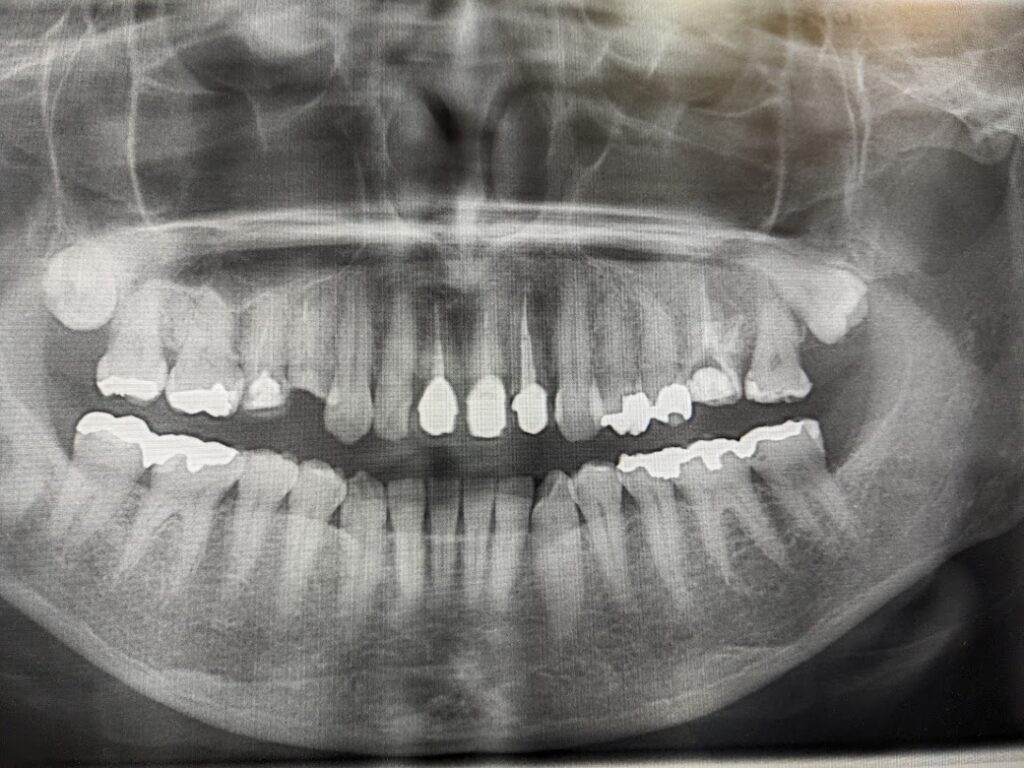

左側上顎洞内にうずら卵大の不透過像をみとめます。左側6は根管充填が実施されています。

左側6の根尖から連続して上顎洞粘膜が挙上されています。上顎洞病変の内部に根管治療材の一部迷入しています。今後残留していると病変に影響を与える可能性も否定できませんでし、病変の増大悪化考えられました。

術後のパントモ写真になります。現在6ヶ月経過していますが上顎洞炎症状も認めず経過良好です。